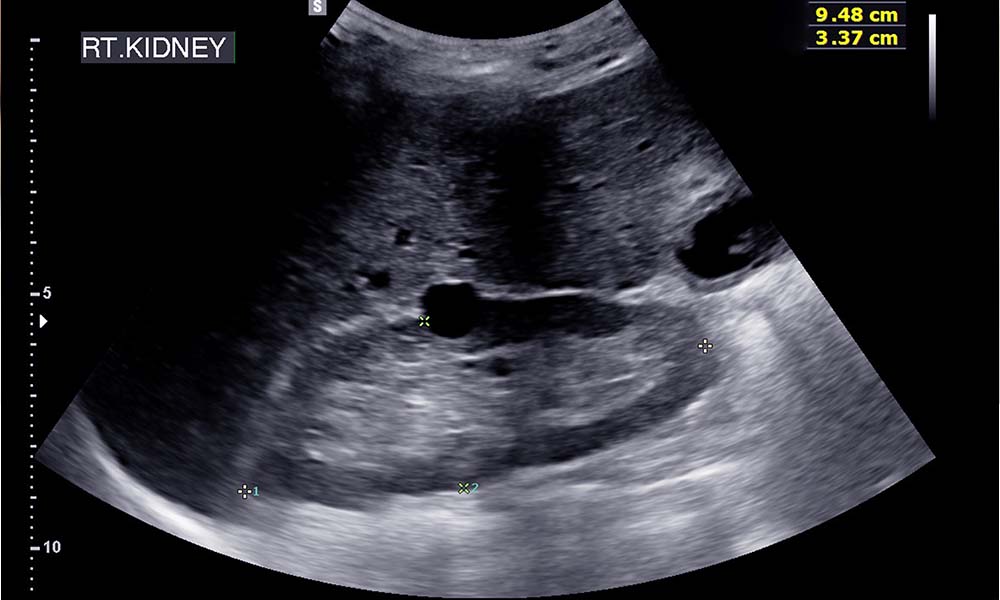

USG układu moczowego służy do oceny stanu nerek, pęcherza moczowego oraz moczowodów, a w przypadku mężczyzn – gruczołu krokowego. Badanie pozwala wykryć:

- zmiany ogniskowe, do których należą torbiele i guzy,

- kamicę nerkową,

- wodonercze,

- zwężenie tętnicy nerkowej,

- zmianę rozmiaru moczowodu,

- zastój moczu.